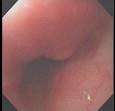

男性,68岁,腹痛1周,便血1天,既往有糖尿病和高血压病史。查体BP170/80mmHg,腹软,左下腹有压痛,无明显反跳痛,肠鸣音减弱。肠镜检查图片如下,...

问题 男性,68岁,腹痛1周,便血1天,既往有糖尿病和高血压病史。查体BP170/80mmHg,腹软,左下腹有压痛,无明显反跳痛,肠鸣音减弱。肠镜检查图片如下,最可能的诊断是 ( )

选项 A、Crohn病 B、肠结核 C、大肠癌 D、溃疡性结肠炎 E、缺血性结肠炎

答案 E